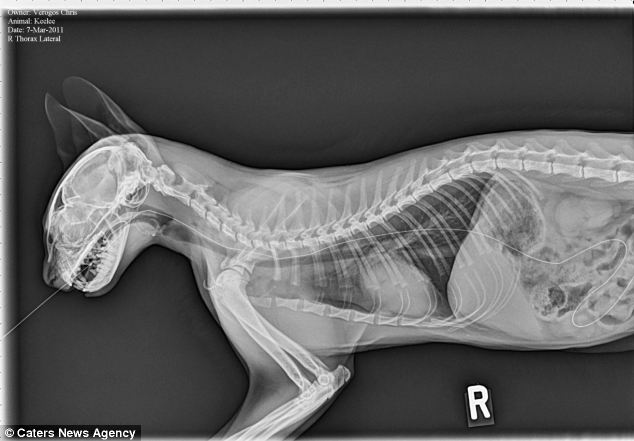

When the vet saw us, she did not seem too worried about Benita, saying that her breathing sounded good and she had good oxygen in her gums. But she wanted to do the x-Ray to see why little Benita was breathing using more of her stomach than her lungs.

The x-Ray confirmed the worst. The vet was shocked that Benita had been able to live this long with such an injury. She had a Herniated Diaphragm. Because of the pressure difference between the two areas the diaphragm separates, Benita had to work very hard for each breath, which is why her breathing looking labored.

The vet showed us the difference between Benita and a healthy cat, we were saddened to see that the area where her lungs are heart are located had been invaded by the organs normally kept back by the diaphragm. The unwelcome do organs were taking up the space her lungs needed to breath.

Benita’s X-Ray

Healthy Cat X-ray (The defined line in the center is the Diaphragm.)